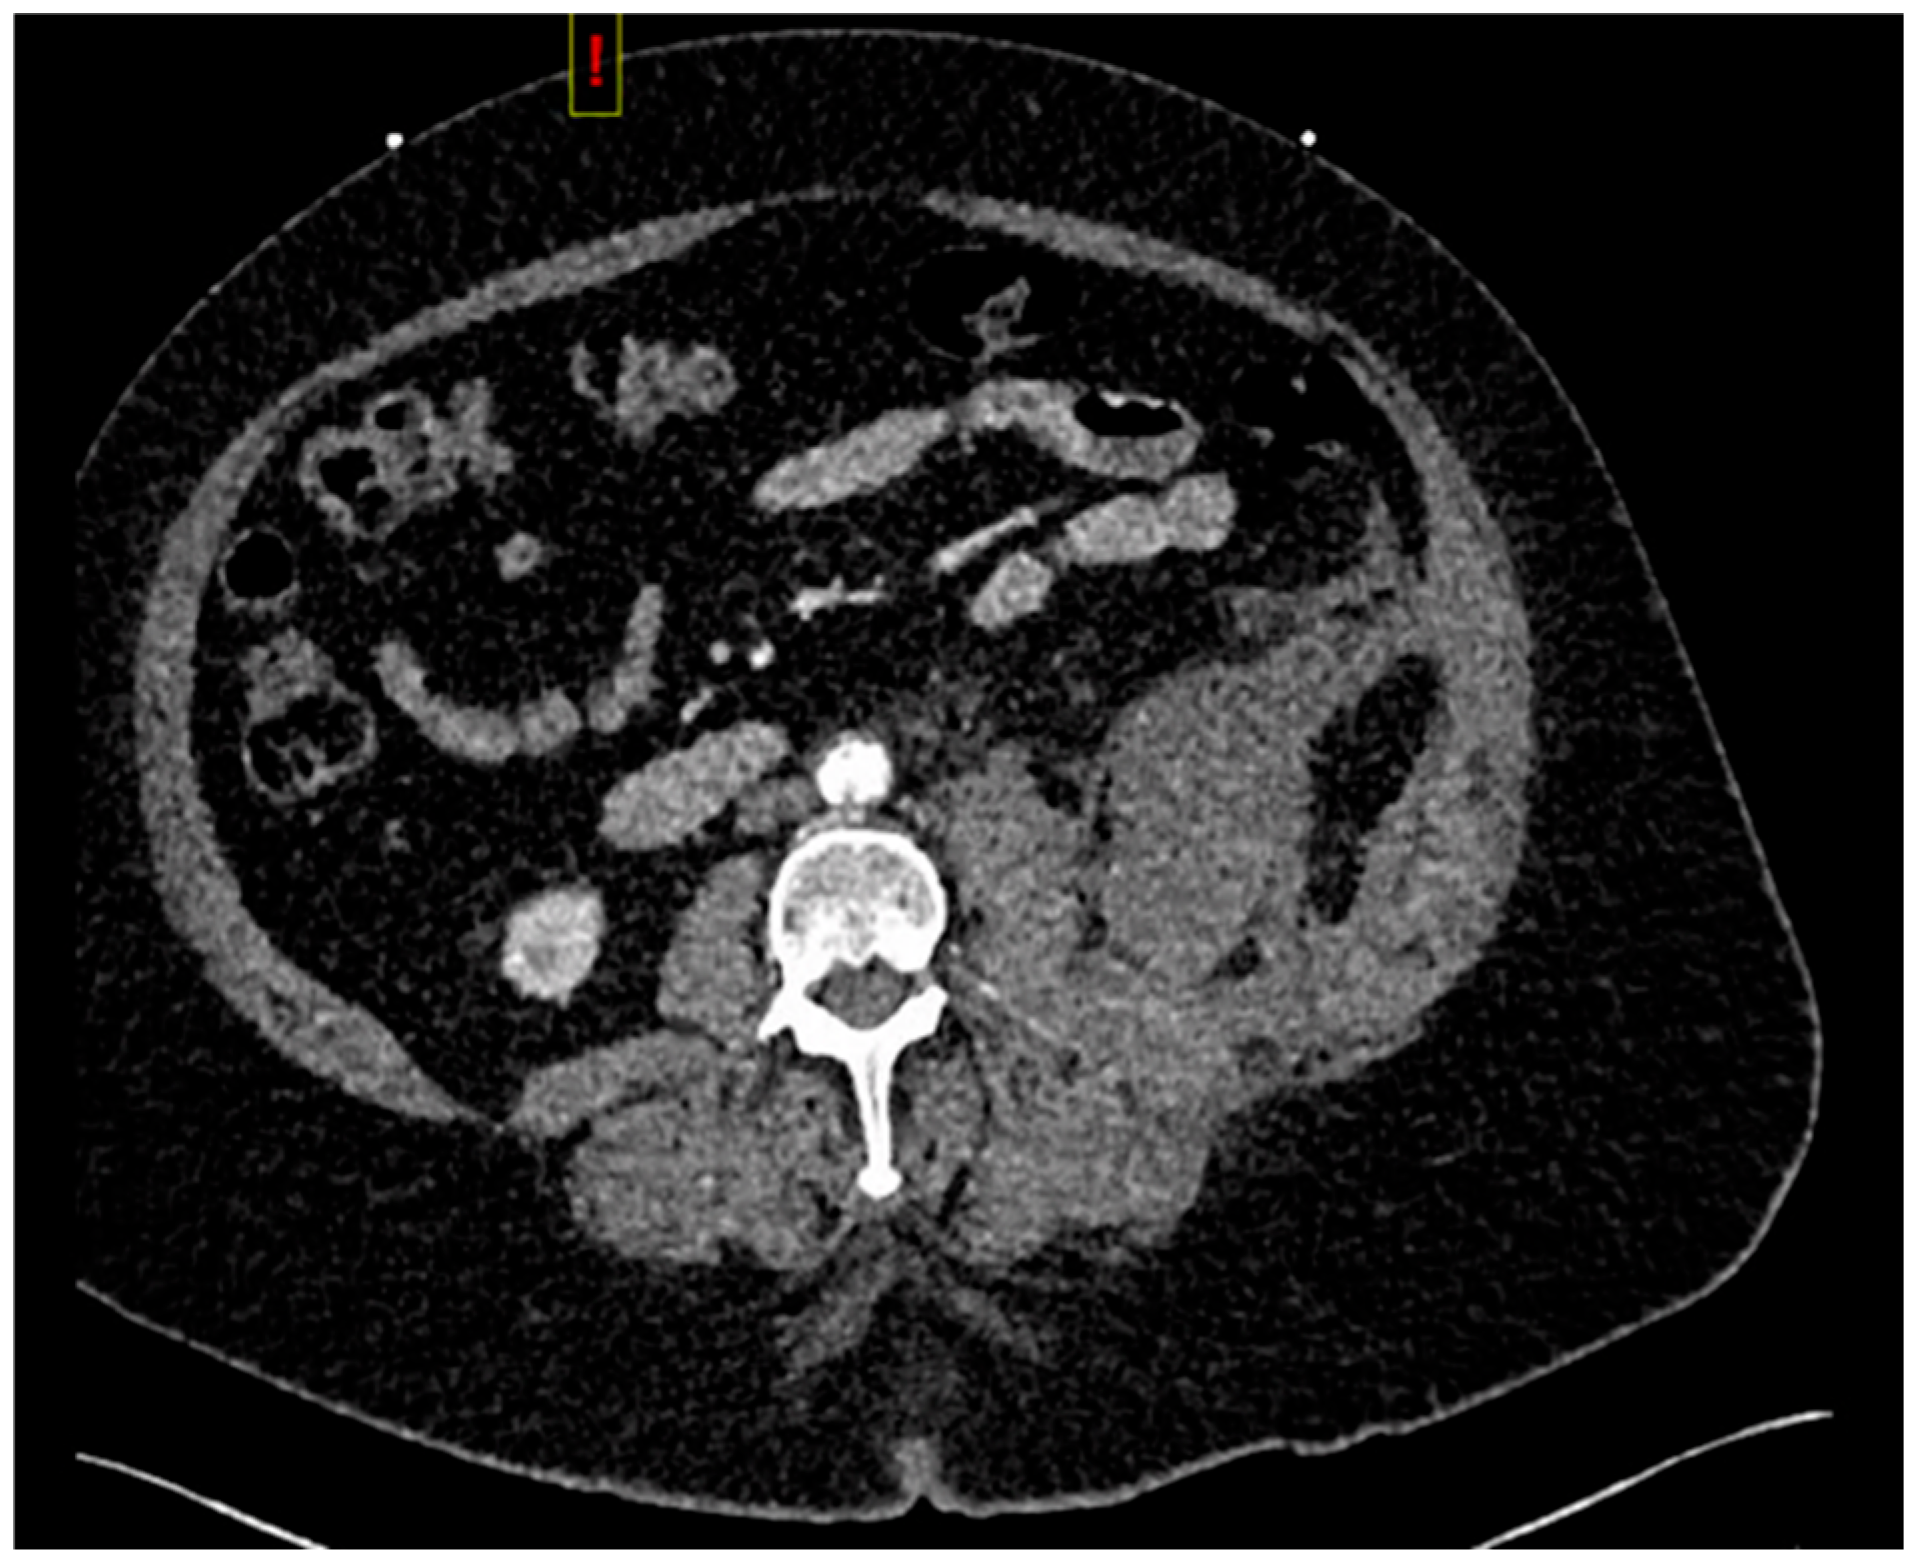

Computed tomography angiogram (CTA) protocol images are displayed below. Figure 1 and Figure 2 correspond to her state prior to tPA administration; notice the 100% occlusive aortic thrombus. Figure 3 and Figure 4 are post-tPA administration, demonstrating the fully restored aortic flow.

Figure 3. CTA in transverse view post-tPA.

The patient was admitted to the ICU for monitoring. On day 2, she began to experience abdominal and flank pain. A repeat CT angiogram of the abdominal aorta and bilateral iliofemoral runoff showed complete resolution of the aortic and bilateral common iliac occlusion; however, the patient had a new retroperitoneal bleed. The heparin drip was stopped, and the patient required a transfusion of 2 units of packed red blood cells for blood-loss anemia. The patient’s hemoglobin levels stabilized without further intervention (and did not require any direct surgical or interventional radiology treatment). The patient ultimately had a full return of function of her lower extremities and was discharged, walking, from the hospital on day 6. Further anticoagulation was deferred due to the patient’s recent retroperitoneal bleed. At her 2-week follow-up appointment, she was noted to be ambulatory, without any neurodeficit.